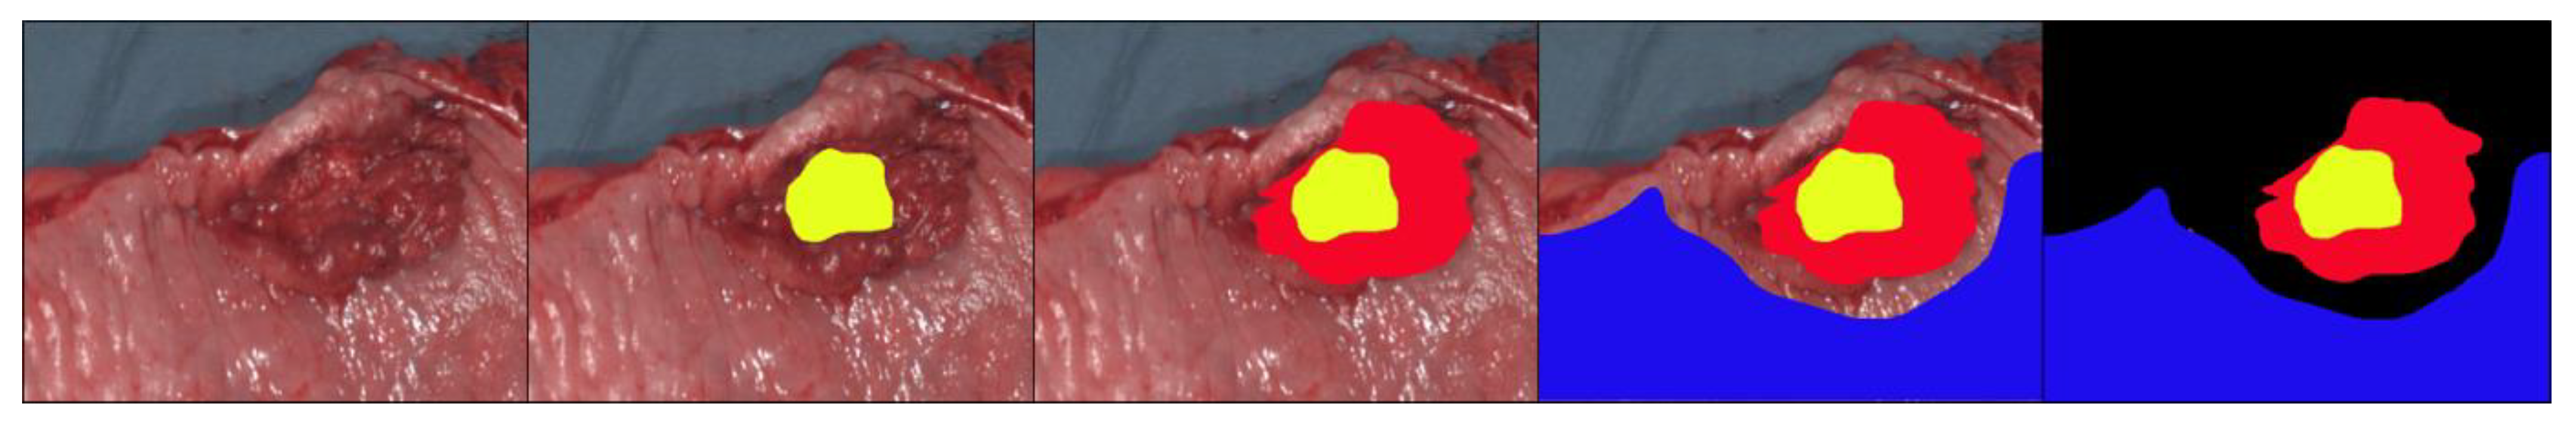

3.2. Classification and Visualization